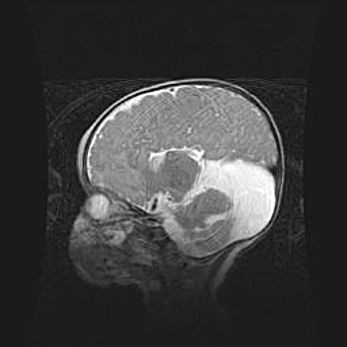

Мальформация Денди-Уокера. Киста задней черепной ямки.

Агенезия мозолистого тела.

Возраст: 2,5 месяца

Вес: 2420 г

Пол: женский

Окружность головы: 37 см

Срок гестации: 32 недели

Мальформация Денди—Уокера — редкий вид патологии ЦНС, представляющий собой врожденный порок развития каудального отдела ствола и червя мозжечка, ведущий к неполному раскрытию срединной (Мажанди) и латеральных (Лушка) апертур IV желудочка мозга. Для этогно синдрома характерна триада симптомов: гипотрофия червя мозжечка и/или полушарий мозжечка, кисты задней черепной ямки, гидроцефалия различной степени. В 70% случаев порок сочетается и с другими аномалиями головного мозга, в частности с агенезией мозолистого тела.